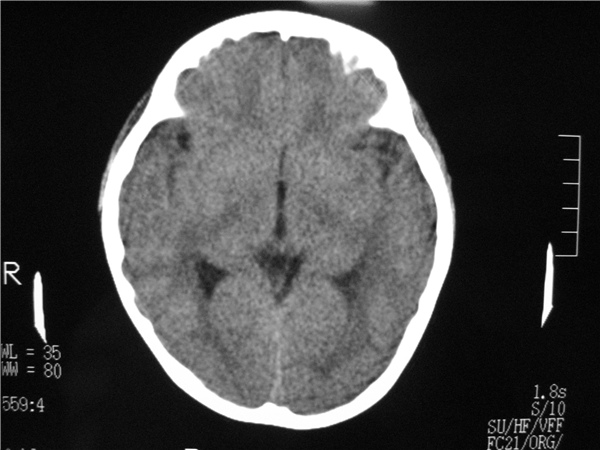

以下是引用随光逐影在2009-8-1 14:17:00的发言:[br]透明隔囊肿与vergae腔并存。

以下是引用zjzjr在2009-8-1 14:51:00的发言:[br]五、六脑室形成。